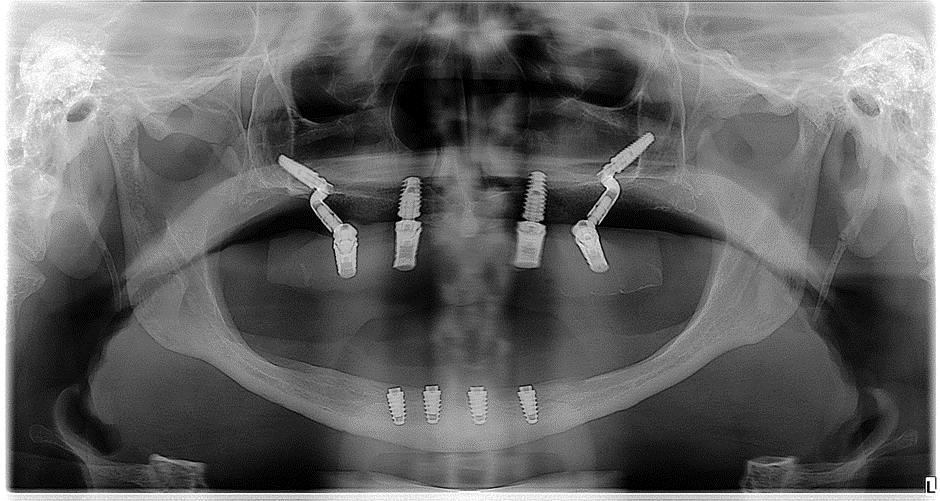

Foi feito então a avaliação clínica e de exames complementares de imagem (Figura 2).

Após planejamento do caso, foi proposto e aceito pelo paciente a realização da reabilitação da maxila com dois implantes, utilizando dois implantes convencionais e dois em osso zigomático com o componente pilar Z. A publicação do caso foi autorizada mediante assinatura do Termo de Consentimento Livre Esclarecido (TCLE).